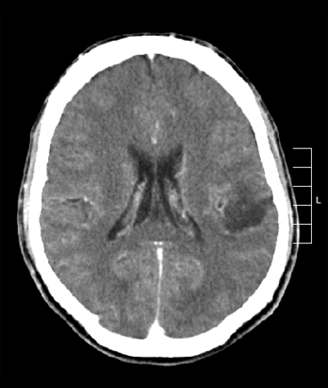

Glioma of the left parietal lobe, CT scan with contrast enhancement; source: Ninilak, Wikimedia Commons